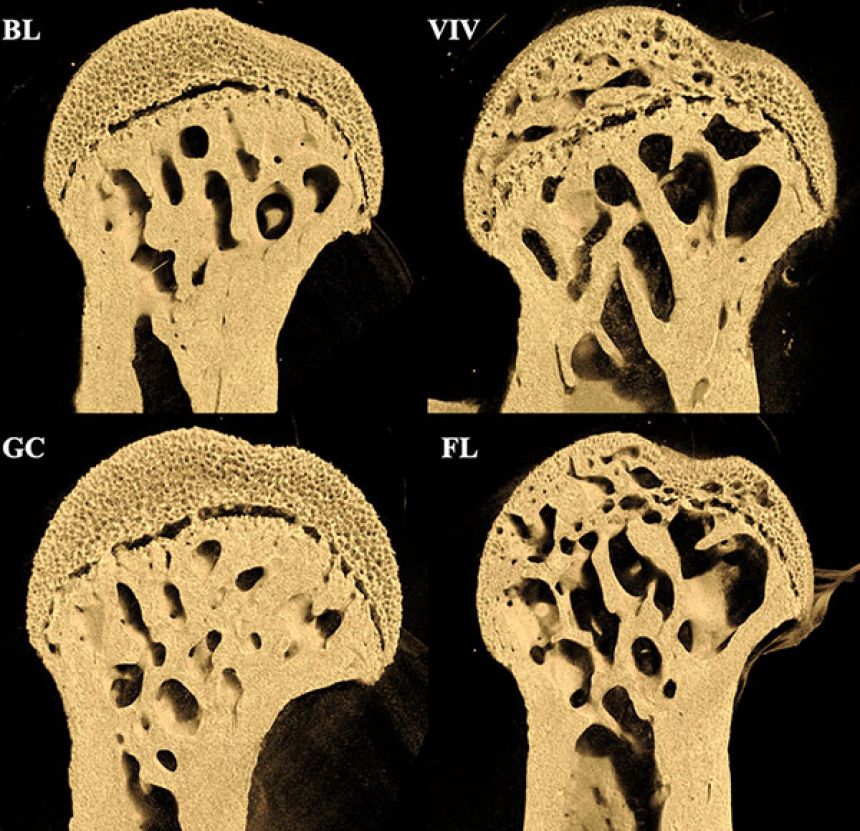

37日間の宇宙滞在後、マウスの骨には驚くべき変化が現れた。骨密度の低下が特定の部位で著しくスカスカになっていたのだ。

その結果、骨の密度が大きく低下し、スカスカになるという恐ろしい現象が確認されたのだ。まるでスイスチーズのようだ。

ただしその影響は、どの骨にも一様に働いたわけではなく、部位によってダメージの大きさは異なっていたという。

たとえば、後ろ足の大腿骨(だいたいこつ:太ももの骨)では大きな穴がいくつも確認された。とりわけ骨頭(股関節側の丸い部分)や膝関節とつながる両端部分の密度の低下は大きなものだった。

その一方、背骨の腰の部分(腰椎)はほとんど影響がなかった。

たとえば、大腿骨の頸部は、国際宇宙ステーションでの滞在37日後、内側の海綿骨髄が大幅に減少していたのに対して、外側の部分はかなりしっかりしていた。